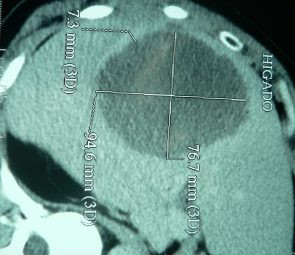

Drenaje percutáneo de absceso hepático

Envíado por Dr. Carlos Miguel Zavaleta Consuegra